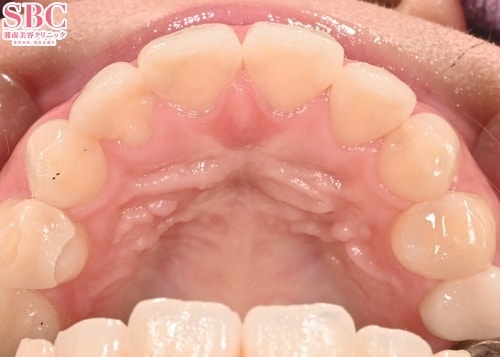

施術前

施術後7ヶ月後

「健康な歯はできる限り残して治療する」というこだわりがあります。 大切な歯を抜かずに矯正を行うことで、 お客様の身体的負担を軽減し、ご自身の歯で長く快適に過ごしていただけるよう努めています。見た目が美しくなるようにマウスピースの設計をすることはもちろんですが、それだけでなく、お口全体の健康を考慮した治療計画を実施しています。

マウスピース矯正で「歯並びを綺麗に並べる」、「口元を引っ込める」という部分にだけ焦点をあてて矯正を進めてしまうと、お顔のほうれい線が目立ったり、鼻の下が長くなってしまうことがあります。 マウスピース矯正で噛み合わせ等の「機能面を整える」ことはもちろんですが、口元だけに着眼してマウスピースの設計をするのではなく、 お顔全体のバランスを考慮して「お顔全体に対しての口元』と言う広い視野でマウスピースの設計をすることにこだわっています。

マウスピースの設計で無理に歯を動かすようなリスクのある設計は行いません。 矯正終了後も永くご自身の歯で過ごしていただくことを見据えているからこそ、歯に無理 のない治療計画をすることにこだわっています。また、マウスピース矯正は自己管理型の矯正方法ではありますが、医師による経過観察がしっかりと行われることが重要であると考えます。 経過観察で有害事象の早期発見や、歯が計画通り動いていない場合のマウスピースの交換周期の調整等を行い、お客様の理想の歯並びや矯正期間を実現するサポートを徹底しています。